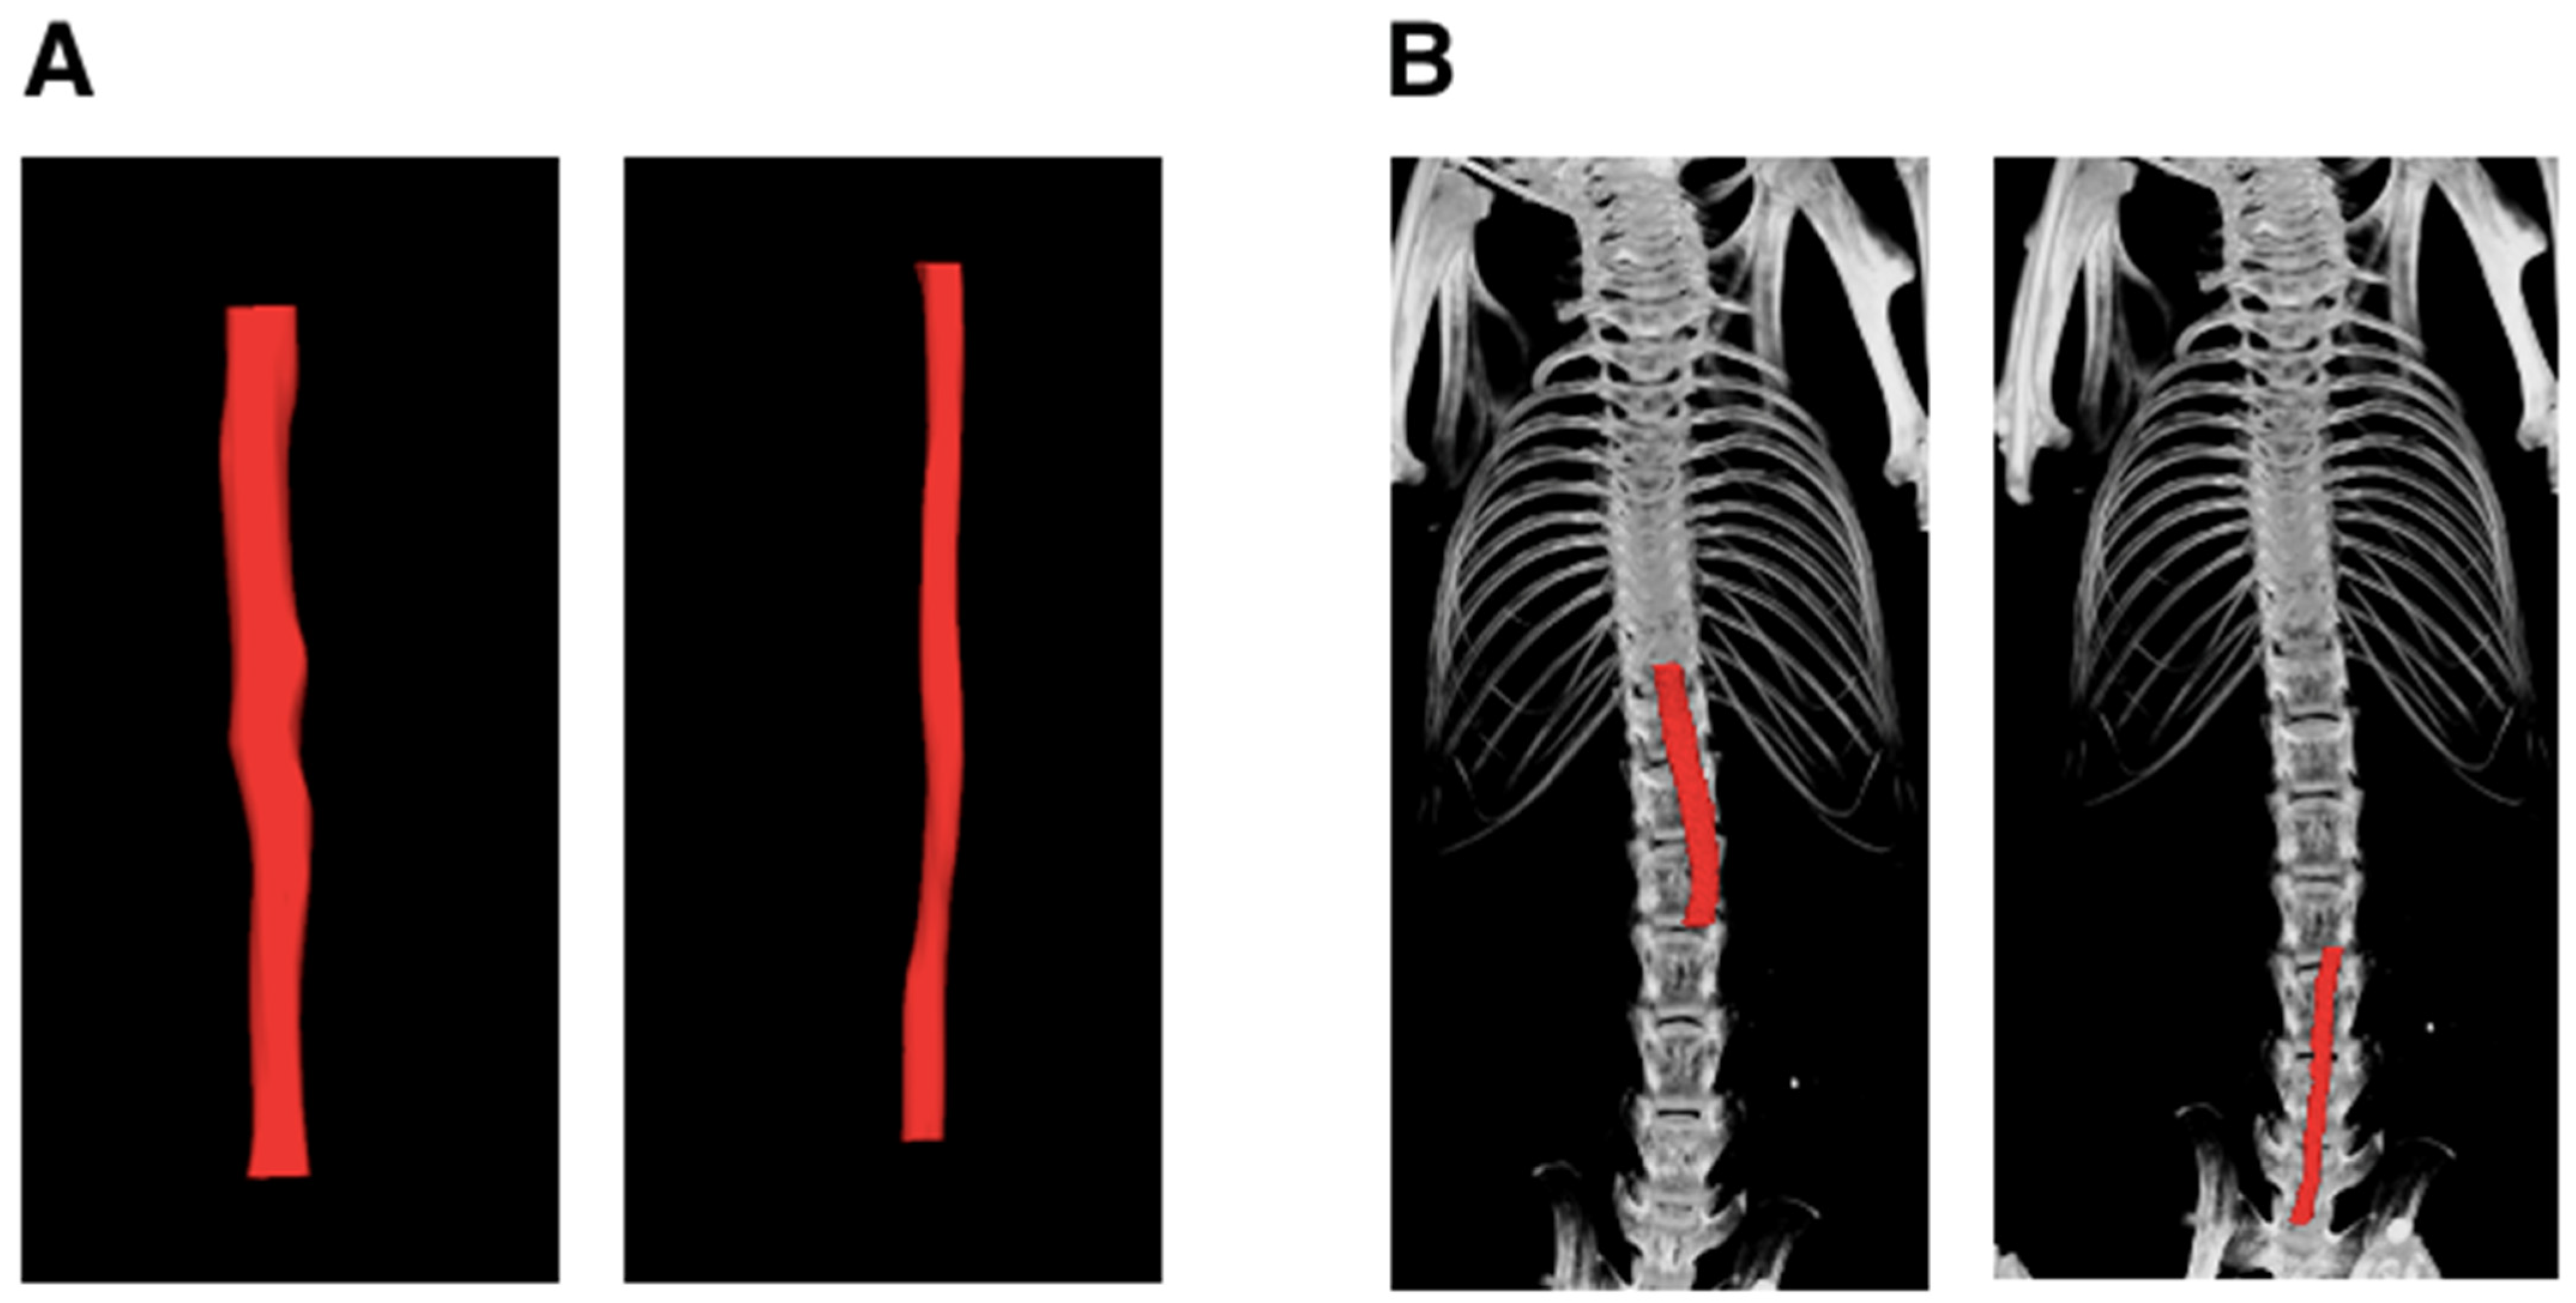

2.3. Micro-Computed Tomographic Angiography (μCTA)

3. Results

3.1. Inter-Observer and Intra-Observer Variability in μCT